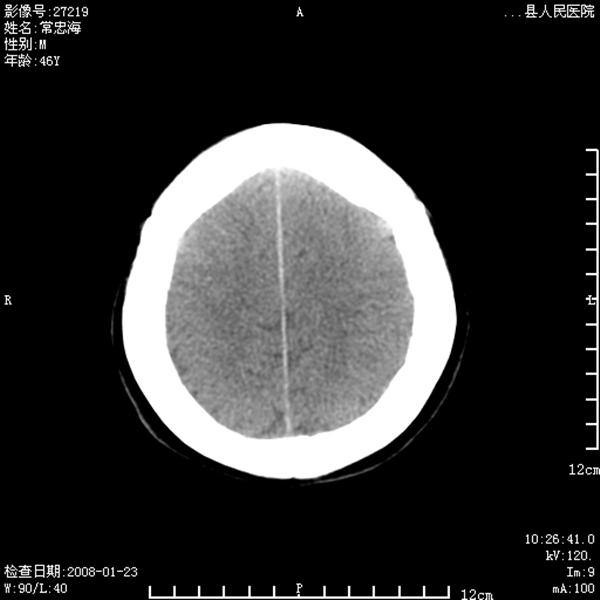

以下是引用江边学者在2008-4-19 22:26:00的发言:[br]1.胼胝体发育不良。[br]2.右侧眼球痨。[br]3.右侧颜面部软组织挫伤。